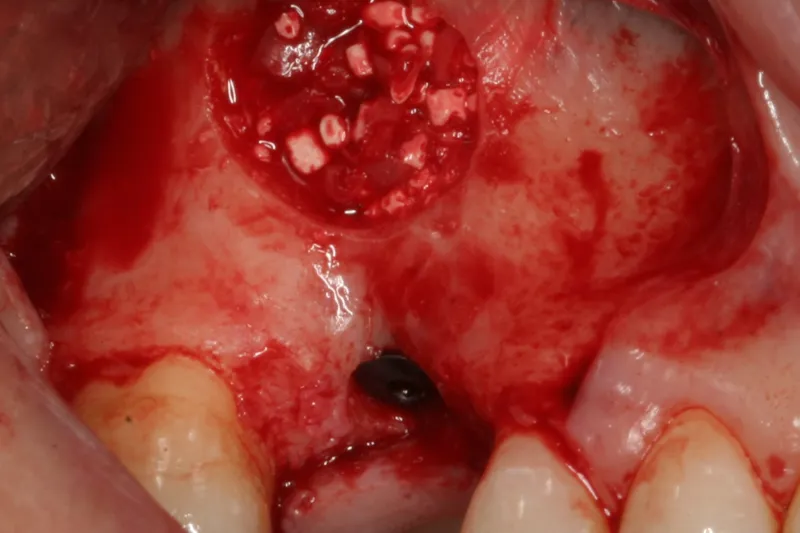

Indsættelse af implantater i den bagerste del af overkæben er ofte vanskeligt eller umuligt på grund af svind af processus alveolaris og pneumatisering af sinus maxillaris efter tandtab. Genopbygning af processus alveolaris kan derfor i mange tilfælde være nødvendig enten før eller i forbindelse med implantatindsættelsen. Sinusløftprocedure med lateral vindueteknik og anvendelse af partikulært autologt knogletransplantat og/eller et knogleerstatningsmateriale er den hyppigst anvendte kirurgiske procedure i maksillens præmolar- og molarregion. Slimhinden i den nederste del af sinus maxillaris eleveres for at skabe et hulrum mellem den oprindelige bund af sinus maxillaris og den eleverede sinusslimhinde, der oftest udfyldes med et transplantationsmateriale.

Protetisk rehabilitering med implantater i den bagerste del af overkæben kan være vanskeligt på grund af svind af processus alveolaris og pneumatisering af sinus maxillaris efter tandtab. Sinusløftprocedure med lateral vindueteknik og et partikulært autologt knogletransplantat og/eller et knogleerstatningsmateriale har været anvendt i snart 40 år til genopbygning af processus alveolaris i den bagerste del af overkæben. Flere oversigtsartikler og metaanalyser har dokumenteret høj overlevelsesrate af såvel suprastruktur som implantat samt forudsigelig nydannelse af knogle og begrænset peri-implantært knogletab.